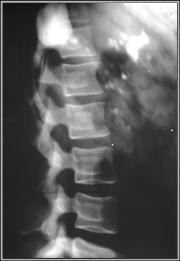

Thorotrast